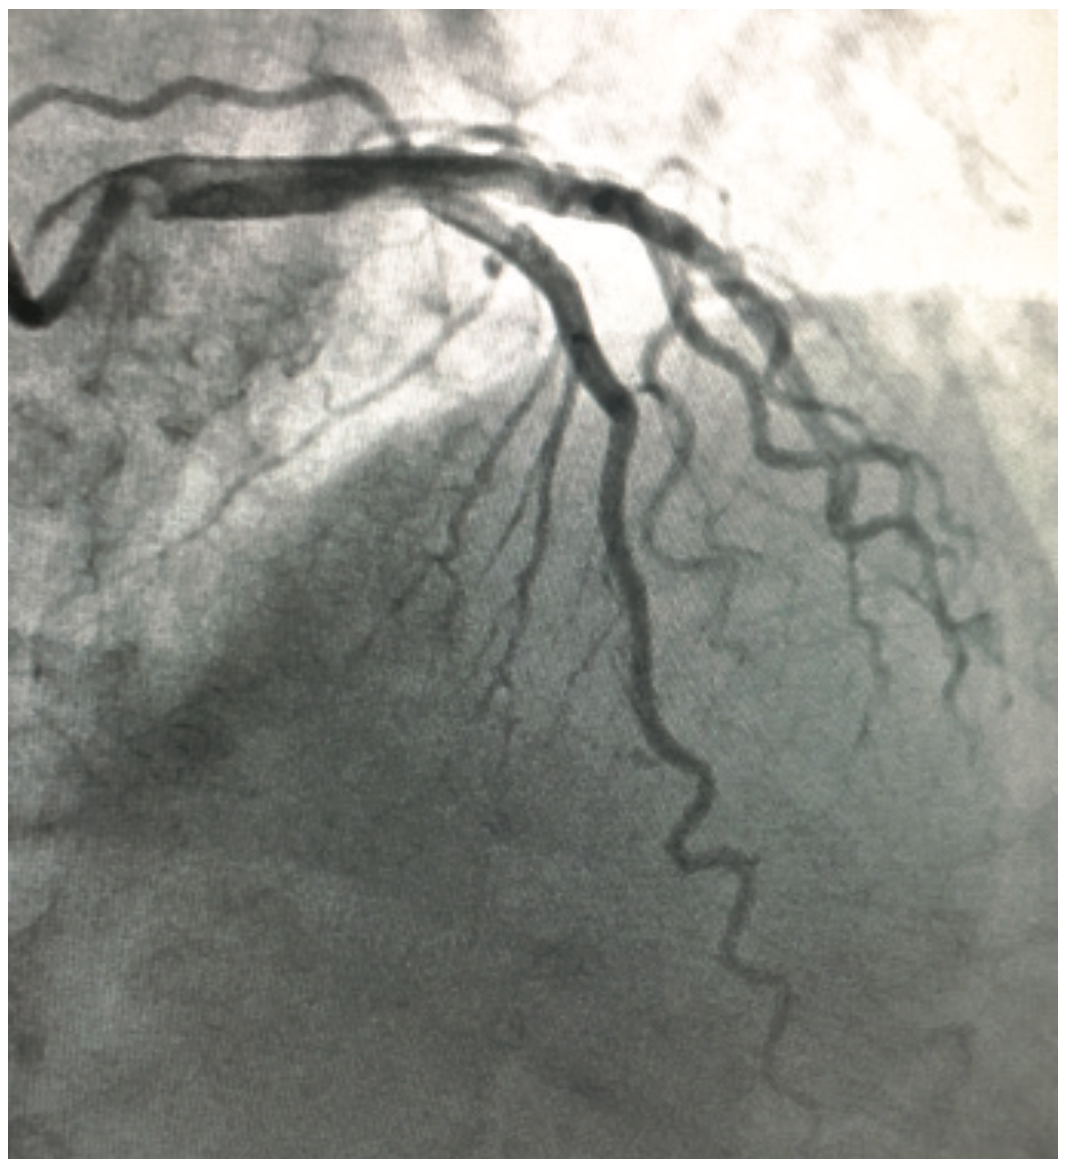

Although not common or rare, coronary bridging (myocardial bridge) is a congenital anomaly where a band of muscle lies on top of a coronary artery instead of below it. As a result, a portion of the vessel is revealed that dips into and underneath the heart muscle, and then back out again. The vessel is open during diastole (Figure 1) and compressed during systole (Figure 2).

Cardiac catheterization via a radial approach demonstrated minimal non-obstructive coronary artery disease, with a bridging effect in the mid LAD (Figures 1-2, Video 1). Optimizing medical management was the course of treatment.